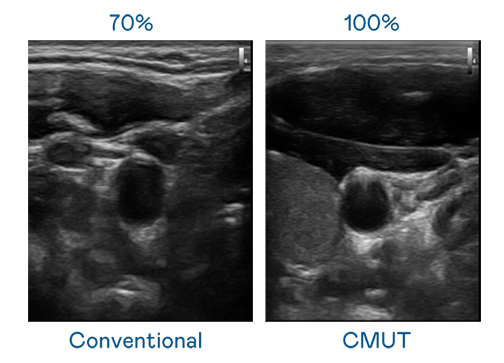

CMUT 技术是一种用电容式微机电元件来产生超音波讯号的技术。与传统 PZT 压电式技术相比,CMUT 频宽增加 30%,更宽频的超音波讯号让影像解析度大幅提升,是实现高影像品质医疗超音波扫描、促进精准医疗发展的关键技术。

大频宽带来超清晰影像

超音波影像的解析度高低,首先取决于探头能发出的讯号频宽。j9九游会真人国际第一 CMUT 可提供高清晰的超音波讯号,提供高频宽、高灵敏度、影像纹理细节更高的超音波影像,协助医护人员缩短影像判读时间及利用精准的医疗影像进行诊断。